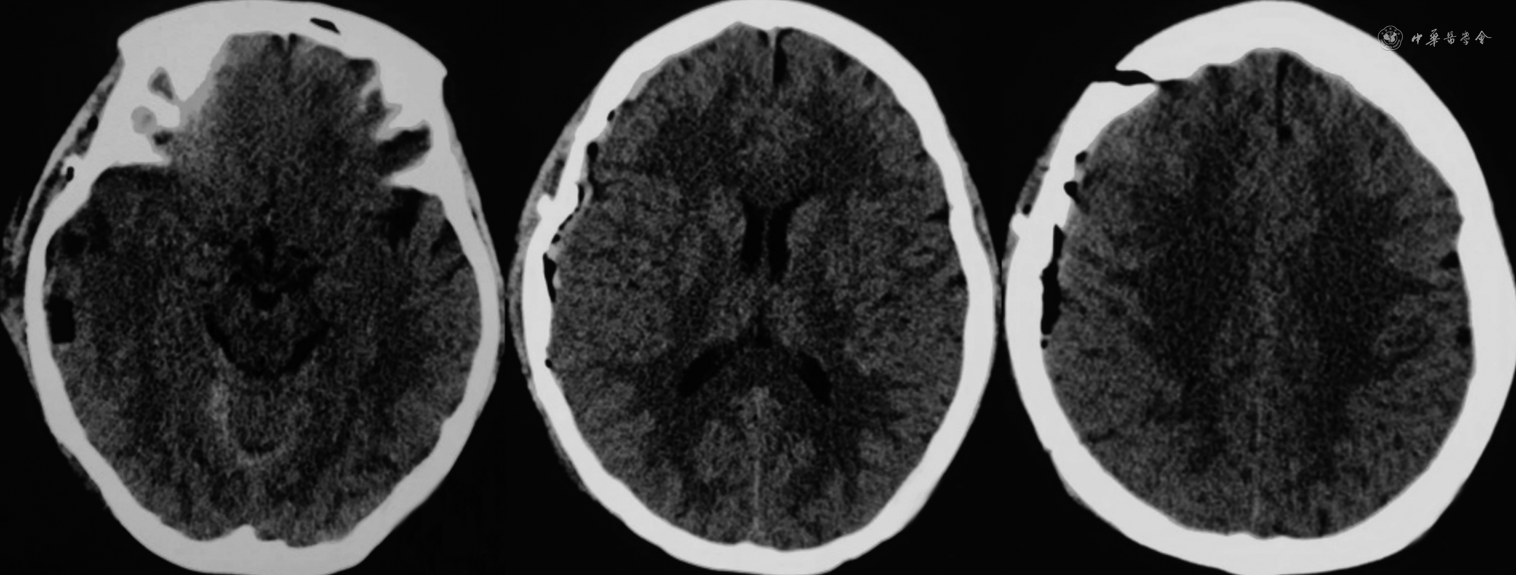

患者女性,55岁,慢性病程。患者自诉于2021年9月初无明显诱因偶发骶尾部疼痛不适感,起初程度轻微,不影响正常生活,后症状迁延,骶尾部疼痛发作频繁且程度加重,严重制约患者日常生活及工作。2021年10月4日入住甘肃省人民医院并于次日完善骶椎MRI检查,结果示骶椎椎管内见一类椭圆形长T1、长T2信号影,长径约2.5 cm(图1)。结合患者病史及影像学资料初步诊断为骶管囊肿。入院体检:骶尾部压痛,其余各项体检结果均未见明显异常。术前完善相关检查,排除手术禁忌证,于2021年10月10日全身麻醉下行后正中入路显微镜下骶管囊肿切除术与脊神经粘连松解术,于麻醉苏醒后返回我科神经重症监护室,予以重症监护,患者嗜睡,轻度恶心,无呕吐,约10 min后患者突发呼之不应,右侧瞳孔散大,直径约5.0 mm,直接及间接对光反射消失,左侧瞳孔直径约2.5 mm,直接及间接光反应灵敏,急予250 ml甘露醇快速静脉点滴并急诊完善头部CT,CT影像学检查结果提示:右侧额顶颞枕部硬膜下血肿,中线由右向左偏移,环池欠清,脑干受压明显(图2)。患者病情危重,遂急在全身麻醉下行右额颞开颅硬膜下血肿清除+骨瓣还纳术,术中未见颅骨骨折、颅内原发性损伤病灶。术后6 h后患者意识状态逐渐恢复,复查头颅CT提示硬膜下血肿清除干净,中线居中,颅内无再出血及梗死表现(图3)。术后采取头高足低位,予以控制颅内压、补液及营养支持等对症治疗后好转离院。定期随访观察并于出院7个月后我院复查头颅MRI提示:右侧额顶颞枕部颅板下片状混杂信号,等T1、长T2信号,脑沟、裂、池未见受压影像,中线结构居中(图4)。患者恢复良好,无明显后遗症。